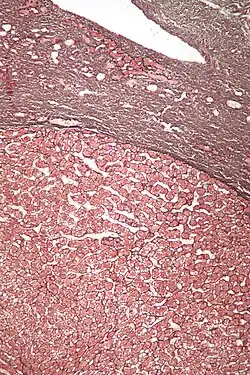

| Micrograph of a hepatic adenoma (bottom of image). H&E stain | |

Pathologic diagnosis

Hepatic adenomas are, typically, well-circumscribed nodules that consist of sheets of hepatocytes with a bubbly vacuolated cytoplasm. The hepatocytes are on a regular reticulin scaffold and less or equal to three cell thick.

The histologic diagnosis of hepatic adenomas can be aided by reticulin staining. In hepatic adenomas, the reticulin scaffold is preserved and hepatocytes do not form layers of four or more hepatocytes, as is seen in hepatocellular carcinoma.

Cells resemble normal hepatocytes and are traversed by blood vessels but lack portal tracts or central veins.